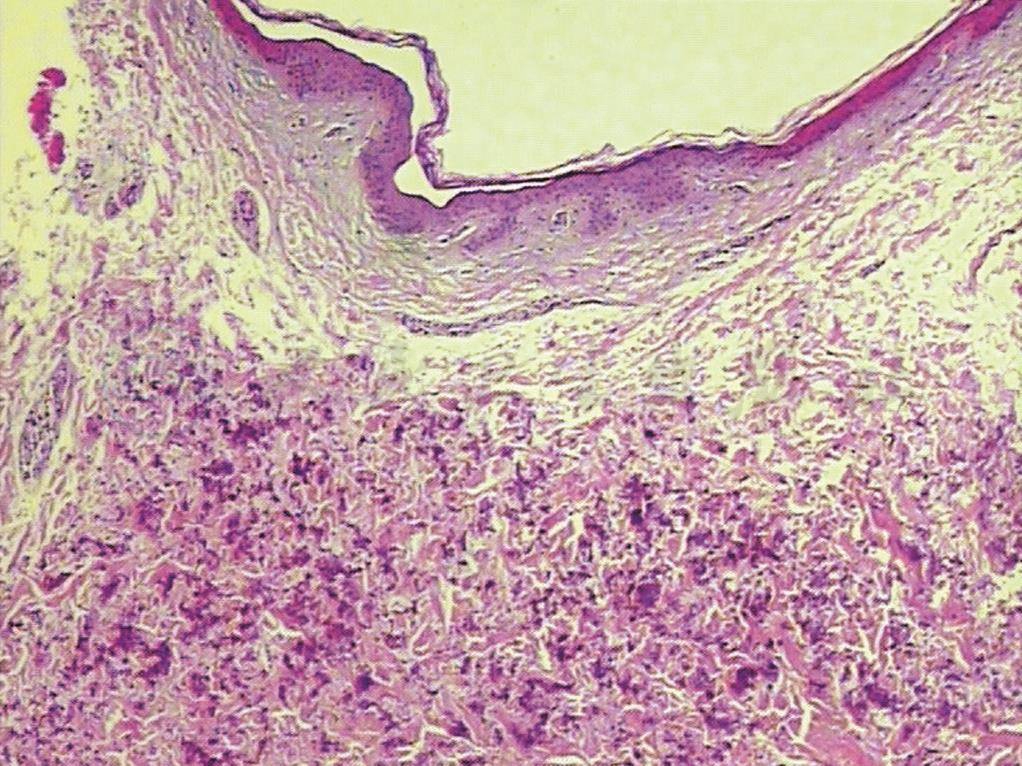

组织病理变化:表皮角化不全、棘层不规则增厚,真皮中部见弹力纤维肿胀、断裂、嗜碱性变。(图1~图2)。

图1 表皮角化不全、棘层不规则增厚,真皮中部见弹力纤维肿胀、断裂、嗜碱性变